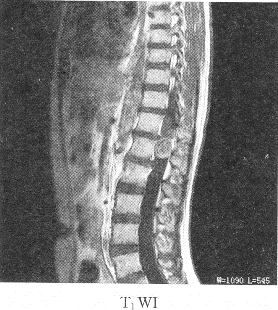

患者女性,23岁,两下肢感觉麻木,结合图像,最可能的诊断是()A: 胸髓积水B: 胸髓血肿C: 室管膜瘤D: 神经鞘瘤E: 椎管内脂肪瘤

患者女性,23岁,两下肢感觉麻木,结合图像,最可能的诊断是()

- A: 胸髓积水

- B: 胸髓血肿

- C: 室管膜瘤

- D: 神经鞘瘤

- E: 椎管内脂肪瘤